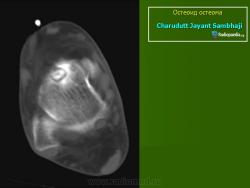

При рентгенологическом исследовании остеоид-остеома обнаруживается как субкортикально расположенный участок окостенения, окруженный ободком остеосклероза, ширина которого увеличивается по мере прогрессирования опухоли. При этом центральная часть опухоли становится менее заметно. Граница между центральной светлой зоной и склеротическим ободком, отчетливая в ранний период, со временем стирается вследствие того, что центральная зона опухоли подвергается оссификации и обызвествлению, которые распространяются центробежно. Рост кортикальных и субпериостальных остеоид-остеом сопровождается также реактивным склерозом- Имеются указания и на то, что если новообразование растет в костномозговом канале, то в соответствующей кости развивается остеопороз. Обычно опухоль легко вылущивается из окружающей кости и макроскопически представляет собой мелкозернистую, красновато-бурую костную ткань. Остеоидную остеому, как правило, удаляют хирургическим путем. Рецидив возможен, но практически не встречаются. Если он и происходит, то спустя 10 лет и позднее после удаления первичного узла опухоли.

Рентгенологическая картина. На обзорных рентгенограммах очаг поражения характеризуется утолщением и уплотнением кортикального слоя кости вокруг небольшого литического гнезда.

Osteoid Osteoma: Subperisosteal, capitatum